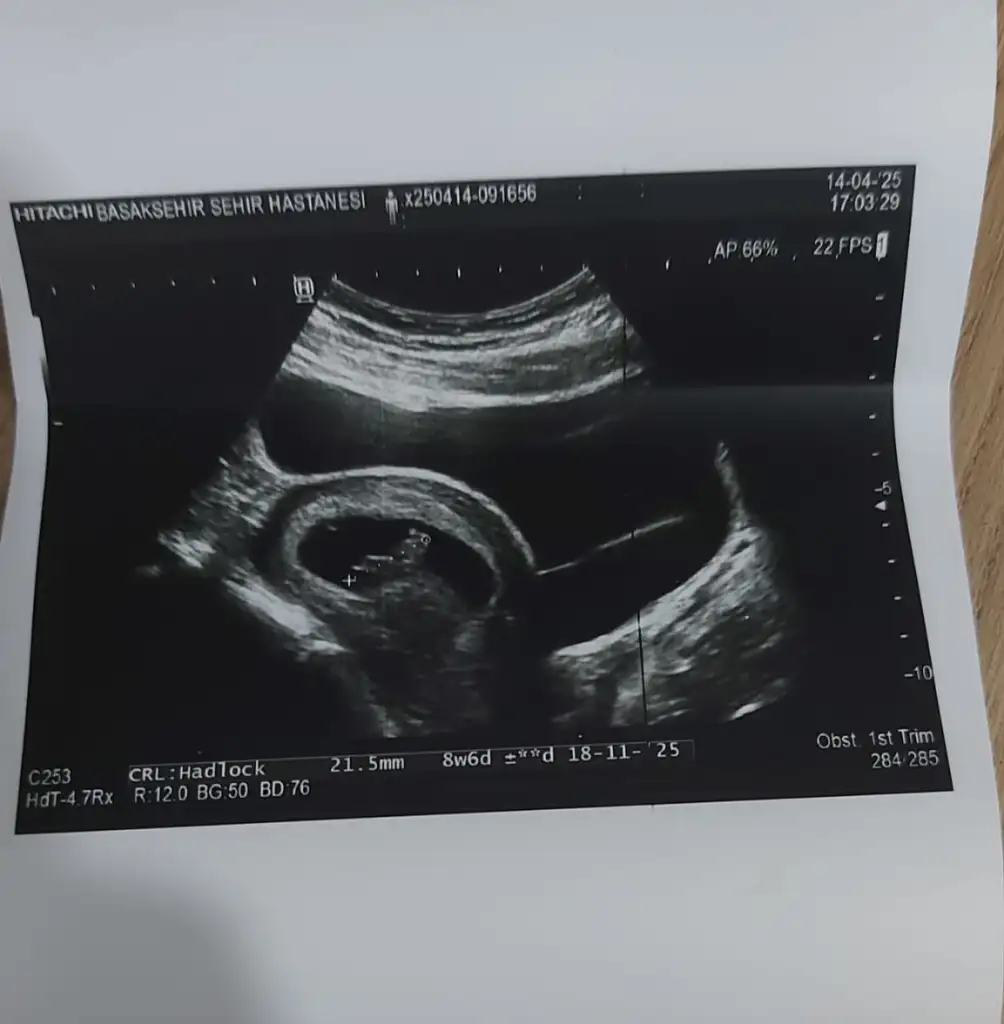

Teşekkür ederim tahmininiz için elimde 6 hafta 4 günlük ultrason görüntüsüde var bebeğimin onada bakıp tekrar tahmininizi söyler misiniz rica etsem

• IMG_1912.webp

IMG_1912.webp

29,3 KB · Görüntüleme: 62